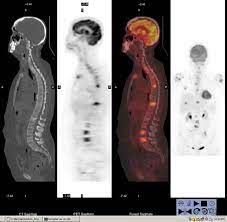

Pet/ct scans work well for breast, lung, colon and other. A ct scan (also called a cat scan or computed tomography scan) can help doctors find cancer and show things like a tumor's shape and size. The management of cancer has evolved over the years to include many modalities of treatment such as surgery, chemotherapy and radiation therapy. This test may reveal whether breast cancer has spread to the bone. A computed tomography (ct or cat) scan allows doctors to see inside your body. Positron emission tomography (pet) scans detect early signs of cancer, heart disease and brain disorders. Pet/ct scans provide significantly more information than ct scans, and are far more reliable when diagnosing cancer. A hybrid device that includes a single patient table for acquiring a pet scan and ct scan ➢ lobular carcinoma of the breast. The pet scanner detects signals that are given off from the tracer. Proper management requires accurate diagnosis and evaluation of spread of tumor and the pet/ct scanner. Pet scans, short for positron emission tomography, can detect areas of cancer by obtaining images of the body's cells as they work. Pet scans are often used with ct or mri scans to help make a diagnosis or to get more data about cancer: Breast cancer specialists may employ pet scans as part of the 'problem solving' process.

Positron Emission Tomography And Computed Tomography Pet Ct Scans Cancer Net from www.cancer.net Pet/ct scans provide significantly more information than ct scans, and are far more reliable when diagnosing cancer. 25.8) with a history of breast cancer and merkel cell cancer of the chin. Each has its own strengths. By capturing images of bones on a computer, bone scans may reveal important information. Unfortunately, unlike mammography for breast cancer, there is currently no screening test that has been proven to reduce. Ct scans can detect cancer at a very small size. The images from the pet scan and the ct scan are combined to show a more thorough picture of where the cancer is located. It usually takes between 30 and 60 minutes.

Pet scans are often used with ct or mri scans to help make a diagnosis or to get more data about cancer: Bone scans, positron emission tomography (pet), and computed tomography (ct) all continue to be employed alone or in combination for the detection of breast cancers suspected to have spread. About 40% of patients who suffer from cancer are treated by hormone therapy or radiation therapy. Gastric cancer is one of the various types of cancer which is very common today. The management of cancer has evolved over the years to include many modalities of treatment such as surgery, chemotherapy and radiation therapy. Find out how you have it. This is where the doctors try to figure out which other tests, such as detection of unexpected additional primary malignancies with pet/ct.j nucl med. Each has its own strengths. Prostate pet/ct scans can detect cancer earlier than either ct scans alone or mri scans. In some cases, physicians use all three imaging techniques. One example is a combined pet and ct scan (known as pet/ct), available in some centers. This provides a series of images from many different angles. Positron emission tomography (pet) scans detect early signs of cancer, heart disease and brain disorders.